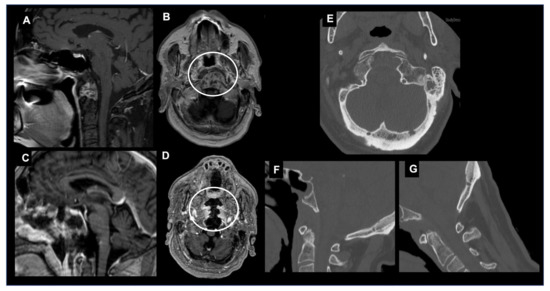

Chordoma, although rare, represents the most common histotype of primary malignant tumors found in this region (Figure 1). Chordomas originate from embryonic remnants of the primitive notochord along the axial skeleton. Chordomas usually occur in adults with a peak incidence between ages 50 and 60, and prognosis is typically poor with a 10-year survival rate of approximately 40% [35]. Less than 5% of chordomas arise in children, and in these cases, they show a more aggressive behavior with a greater incidence of metastasis and mortality, especially when the children are younger than 5 years old [36]. The classic midline clival chordoma is associated with spheno-occipital synchondrosis and can infiltrate the jugular fossa and foramen magnum, which leads to the erosion of the upper cervical vertebrae. The gross entire or nearly total excision of chordomas of the cranial base should be performed whenever possible because of their propensity to recur locally and their low likelihood to metastasize [37,38]. Stereotactic radiosurgery and proton beam therapy have emerged as a valuable adjunct to surgery, and patients benefit from craniovertebral stabilization [39,40].

Figure 1.

Craniovertebral junction chordoma. Sagittal (A) T1-weighted image after contrast and (B) T2-weighted image depicting a large chordoma invading the rhinopharynx and extending into the premedullary cistern.

On CT, chordomas appear as well-defined expansile soft tissue masses that arise from the clivus with associated destructive lytic lesions and occasionally marginal sclerosis [43]. They appear as hypoattenuating heterogeneous lesions with areas of necrosis, hemorrhage and calcifications. Chordomas are iso/ipo-intense on T1-weighted MRI, with small hyperintense foci relative to intratumoral calcifications, hemorrhages or mucus pools. After contrast material injections, a honeycomb pattern of enhancement with intratumoral areas with a low signal intensity is typical. T2-weighed MRIs reveal a bright hyperintensity with heterogeneous hypointensities [38,44,45]. The “thumb sign” is a radiological finding that can be visible when chordomas project posteriorly at the midline and indent the pons [46].